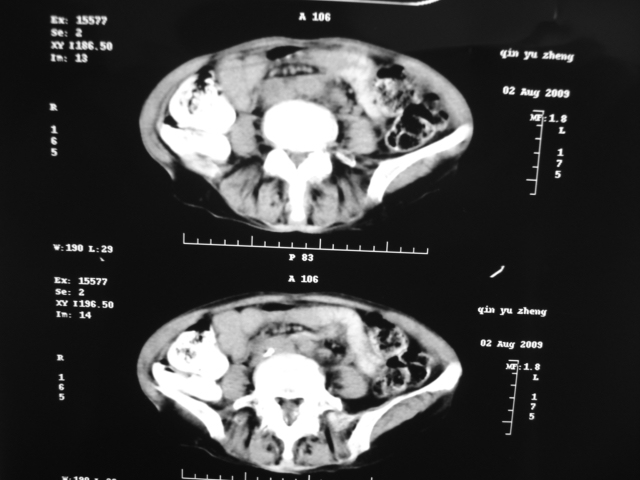

同事奶奶,73岁,腹痛一年,夜晚较重,潜血+++,拒绝增强,考虑左肾ca并腹膜后转移;请各位老师帮忙看看,谢谢!

左肾癌侵及输尿管上段,腹膜后多发淋巴结转移,脾脏钙化灶。至于潜血+++,要考虑消化道病变,本次ct片肠腔未见明显异常。

潜血+++是尿还是便?如果是便,则考虑肾癌侵犯降结肠可能。

1)考虑左肾癌侵犯肾盂并腹膜后淋巴结转移。2)脾脏钙化灶。

查查一胸部,不除外肺癌伴左侧肾上腺,腹膜后淋巴结及左肾转移.